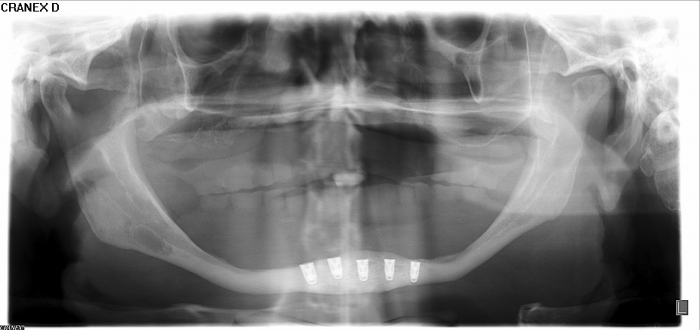

Raio - x Panorâmico inicial, em Julho de 2015